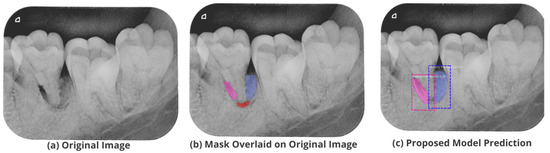

3.5. Comparison with Test Images

The proposed model accurately predicts and localizes the lesions as depicted in Figure 10, Figure 11, Figure 12, Figure 13 and Figure 14. The results indicate that the model makes predictions similar to that of the annotated masks using the periapical radiographic images. Additionally, the proposed model was evaluated based on performance indicators like precision, recall, F1 score, and accuracy for each classified periodontal lesion. The obtained results indicate that the proposed backbone network provides good performance for disease classification. All the test images for the proposed study show a 95% confidence level indicating that the database annotations are in the right direction.

Figure 13.

Test performance for the localization of a ’Primary Periodontal’ lesion.

Figure 14.

Test performance for the localization of ’True Combined’ lesions.